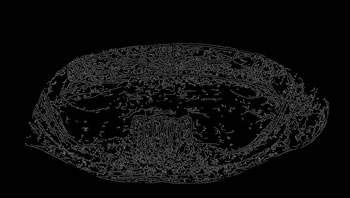

Determining ROI

For each image, after the annotation of the teeth, the buccal region was also annotated, covering the whole region delineated by the contour of the jaws. This process was carried out in view of preserving the area containing all the teeth (objects of interest). Finally, the region of interest (ROI) was determined by multiplying the values of the pixel array elements, representing the original panoramic X-ray image, by its corresponding binary matrix, resulting from the process of oral annotation. Figure 5 illustrates the whole process to determine the ROI of the images.

Figure 5: Determining the ROI of the images.